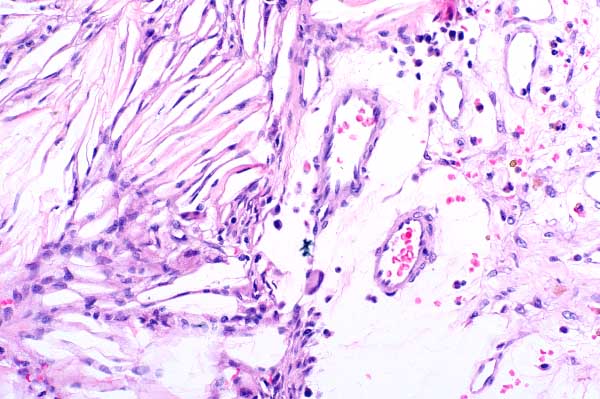

| 20x   |   Hematoxylin & Eosin | ||||

Cholesterol clefts are surrounded by macrophages (sometimes forming multinucleated giant cells (arrows)).